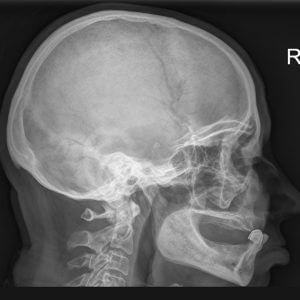

Рентгенография височных костей по Шюллеру (со снимком)

Рентгенография височных костей - это исследование внутренней структуры височной кости и полости среднего уха методом рентгеновского облучения.

Специализированная методика обследования по Шюллеру позволяет обнаружить очаги воспаления и локализацию объемных образований.

Рентгенография височных костей показывает:

- размер, форму и структуру суставных поверхностей височной кости и нижней челюсти

- целостность височной кости

- симметричность височного сустава

- размер межсуставной щели

- наличие образований

- дегенеративно-дистрофические изменения в суставе